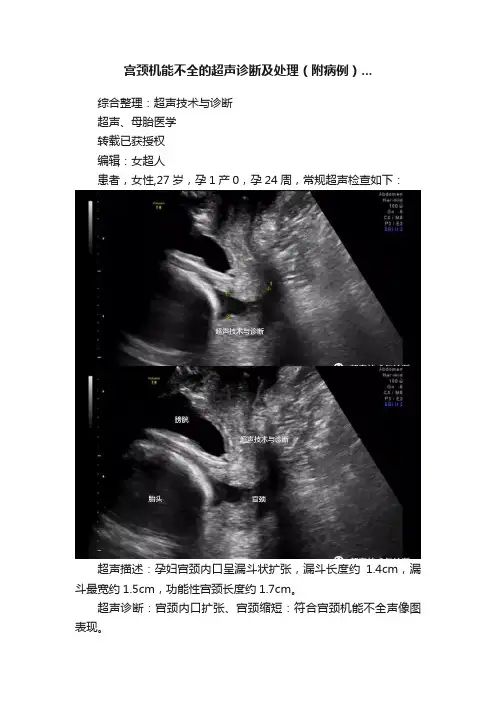

宫颈机能不全的超声诊断及处理(附病例)...综合整理:超声技术与诊断超声、母胎医学转载已获授权编辑:女超人患者,女性,27岁,孕1产0,孕24周,常规超声检查如下:超声描述:孕妇宫颈内口呈漏斗状扩张,漏斗长度约1.4cm,漏斗最宽约1.5cm,功能性宫颈长度约1.7cm。

超声诊断:宫颈内口扩张、宫颈缩短:符合宫颈机能不全声像图表现。